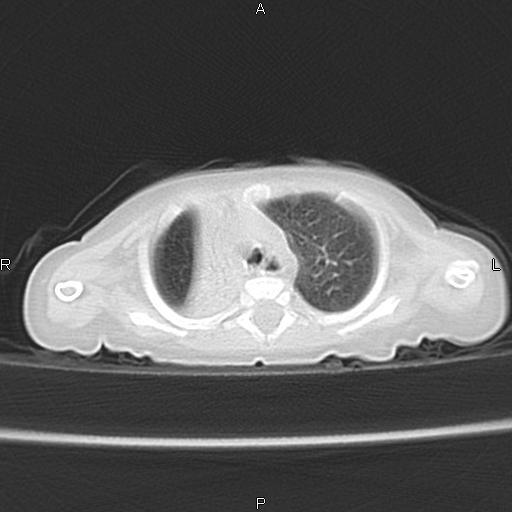

以下是引用aa13877358820在2010-7-26 12:35:00的发言:[br]男性,三个月,卧位胸片,咳嗽、气促、发热14天,两肺闻及细小水泡音。[br]

以下是引用jsdtd在2010-7-26 14:42:00的发言:[br]胸腺呈帆状,体位所致,没事。